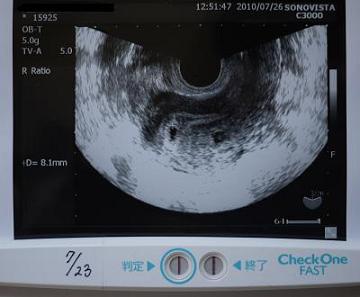

5周0日の胎のうと陽性反応。